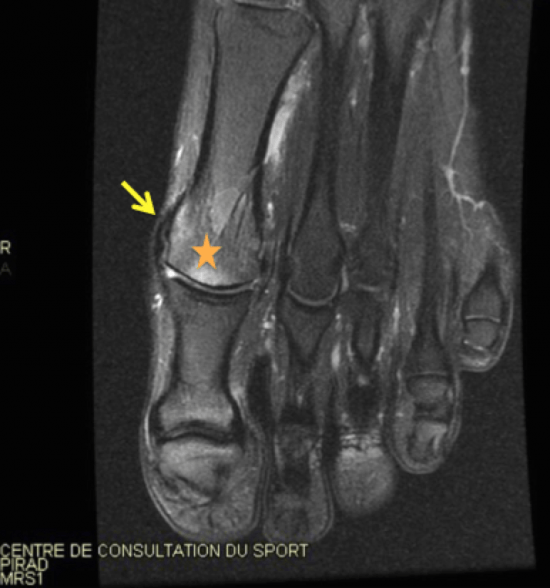

Turf toe ou rupture de la plaque plantaire de l’articulation Lesion Plaque Plantaire The lesser toe plantar plates also provide joint stability and articular surface protection. When discussing plantar plate pathologies, clinicians must recognise two categories of injuries: They are essentially a form of. Le test de lachman peut aider à différencier les lésions de la plaque plantaire en saisissant l’orteil et en le poussant vers le haut. La plaque plantaire est une. Lesion Plaque Plantaire.